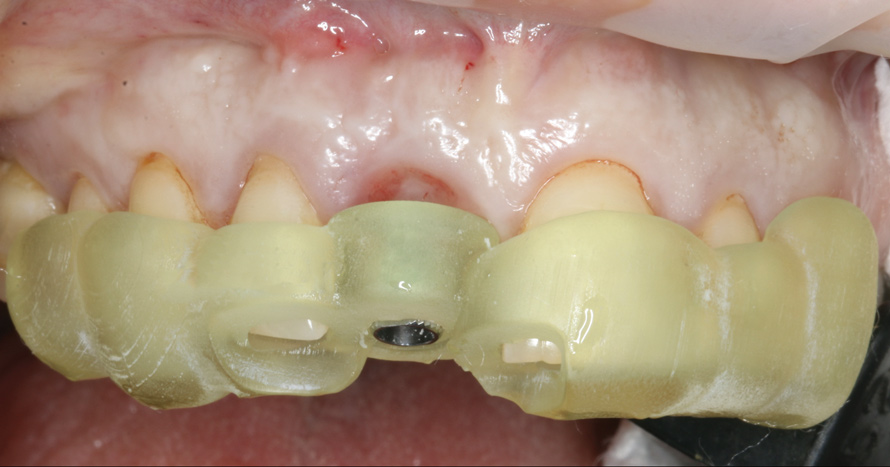

Temporization and Final Restoration

The patient was postoperatively evaluated at 1-, 2-, 4-, 8-, and 12-week recall appointments. The sutures were removed at the 2-week appointment, and the patient was instructed to rinse twice daily and avoid brushing the anterior maxilla. Prior to provisionalization of the implant, the site was allowed to heal for 6 months, during which time the patient was temporized with another Maryland bridge. At the 6-month recall appointment, full mouth periodontal maintenance was completed, and an implant-retained acrylic provisional restoration was placed (Figure 23 through Figure 25). An acrylic provisional restoration allows for soft-tissue attachment while preventing apical migration of the gingival margin. After a 3-month provisionalization period, the final prosthesis was delivered (Figure 26 through Figure 29), and the patient was scheduled for ongoing 3-month recall appointments for periodontal maintenance.

23. Facial view, distal view, and radiograph of the acrylic implant-retained provisional restoration placed at the implant uncovering surgery to contour the soft-tissue profile for final restoration. Critical and subcritical contours follow the anatomic crown profile as seen in both the mesiodistal and buccolingual dimensions.

Figure 23

(24.) Facial view, distal view, and radiograph of the acrylic implant-retained provisional restoration placed at the implant uncovering surgery to contour the soft-tissue profile for final restoration. Critical and subcritical contours follow the anatomic crown profile as seen in both the mesiodistal and buccolingual dimensions.

Figure 24

(25.) Facial view, distal view, and radiograph of the acrylic implant-retained provisional restoration placed at the implant uncovering surgery to contour the soft-tissue profile for final restoration. Critical and subcritical contours follow the anatomic crown profile as seen in both the mesiodistal and buccolingual dimensions.

Figure 25